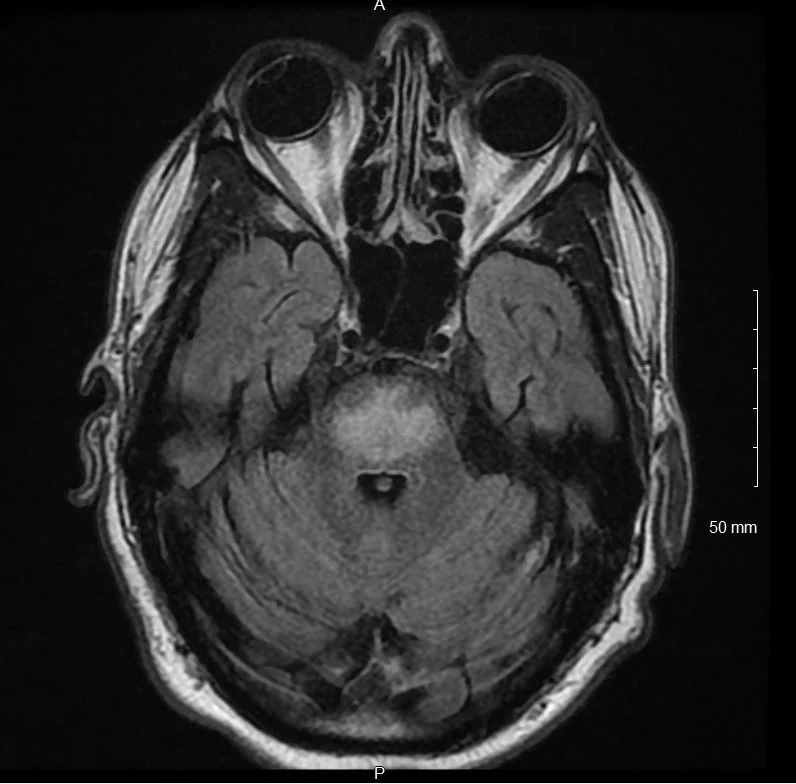

Brain resonance image showing generalized parenchymal volume What Does Volume Loss Mean On A Brain Mri Brain volume loss measured from magnetic resonance imaging (mri) is a marker of neurodegeneration. parenchymal volume loss is a term in the field of medical imaging, indicating the reduction in the volume of. when there is brain volume loss, it’s called atrophy. brain atrophy may be present in tbi with visually apparent volume loss and encephalomalacia in. What Does Volume Loss Mean On A Brain Mri.

From radiopaedia.org

Image What Does Volume Loss Mean On A Brain Mri Brain volume loss measured from magnetic resonance imaging (mri) is a marker of neurodegeneration. parenchymal volume loss is a term in the field of medical imaging, indicating the reduction in the volume of. this typically refers to what is visible on an mri brain scan as “white patches” in the white matter structures of the brain, as seen. What Does Volume Loss Mean On A Brain Mri.